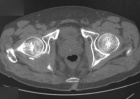

72 year old man with R hip pain since fall in 12/05

Zoom image: Radiological image Radiological image.